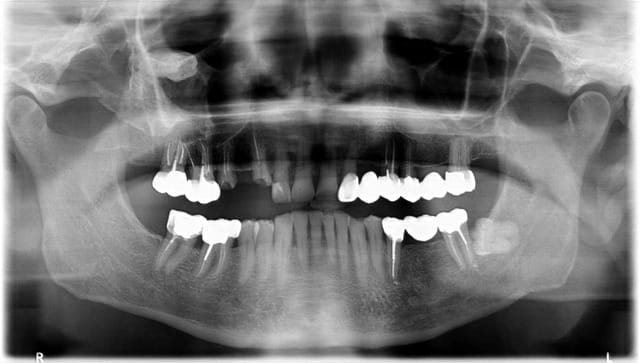

je commence a commenter la pano au patient et d'un coup je la vois mais j'ai failli la rater !!! comme quoi tjs bien regarder le reste AVANT les dents

les d...ents dans le nez !

Sans rigoler, c'est ça qu'ils appellent dent ectopique?

Par habitude, je me suis demandé ce qui pouvait poser problème sur la dent de sagesse... avant de relire le titre et regarder l'opposé de la radio.

On peut dire qu'elle ne saute pas aux yeux. (ha...haha...)

le patient est au courant et me dit que "elle est au milieu du crane ....". Est ce qu'un confrere a pu provoquer cela? On m'a dit qu'il y avait un risque de mettre une DS sup ds la fosse ptérigoide. Mes conaissances anat étant un peu limitées sur cette zone, je ne sais pas ou l'on verrait la dent sur une radio. En espérant que ça reste asymptomatique.

Plus une dent ectopique sinusienne qu'une dent projetée qui serait pas à cette position mais plus dans la zone de l'atm (fosse infra-temporale) ou tubérosité (fosse pterygo)

Un cbct est demandé!

Si dent projetée, pas sur qu'un maxillo s'y risque...zone dangereuse et très difficile d'accès

S'il n'y a pas de symptomatologie l'indication d'extraction ne se pose même pas.

ça sent quand même la dent refoulée dans la fosse ptérygo-maxillaire même si c'est rare de les voir si haut.